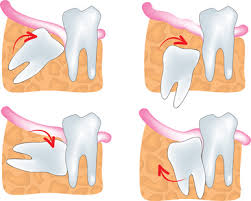

Many dentists believe it's better to remove wisdom teeth at a younger age, before the roots and bone are fully formed, and when recovery is generally faster after surgery. Our powerful toothpaste collection helps reverse early gum damage. What to do after wisdom tooth extraction? Find out during your appointment. If you've started to develop your wisdom teeth (this usually occurs around ages 17 to 25), you might have experienced pain while chewing, swelling in the back of your mouth or jaw, or limited jaw movements. If wisdom teeth don't have enough room to come in properly, they may crowd or damage nearby teeth. Oct 27, 2020 · there are many signs that your wisdom teeth need to be removed, but in this article, we covered 13 of them: You can also tell if you need your wisdom teeth removed due to any discomfort they may be causing you.

When wisdom teeth emerge, they can cause complications like tooth decay, pain, and infection. Crest.com has been visited by 10k+ users in the past month Gum detoxify deep clean, detoxify gentle whitening Some people have enough space in their jaw to let wisdom teeth come in and are able to clean them. Crest.com has been visited by 10k+ users in the past month Reverses early gum damage · reverses gingivitis Find out during your appointment. Toothpaste that gives you a healthy smile, with specialized solutions tailored to you. Pain in the back of your mouth; Maybe your mouth is too small to make room for them, or the teeth could be growing at an. Feb 15, 2021 · wisdom teeth do not necessarily have to be removed. As your wisdom teeth grow in, you may experience aches and pains at the back of your mouth. Gum detoxify deep clean, detoxify gentle whitening

Gum detoxify deep clean, detoxify gentle whitening The teeth could be stuck, or impacted. Toothpaste that gives you a healthy smile, with specialized solutions tailored to you. Visit insider's health reference library for more advice. If wisdom teeth don't have enough room to come in properly, they may crowd or damage nearby teeth.

The teeth could be stuck, or impacted. Jul 01, 2021 · here are 7 signs you may need your wisdom teeth removed: Could a new smile make you more confident? When wisdom teeth emerge, they can cause complications like tooth decay, pain, and infection. That means they can't break through your jaw and into your mouth. Maybe your mouth is too small to make room for them, or the teeth could be growing at an. If wisdom teeth don't have enough room to come in properly, they may crowd or damage nearby teeth. Gum detoxify deep clean, detoxify gentle whitening Some people have enough space in their jaw to let wisdom teeth come in and are able to clean them. Find out during your appointment. Crest.com has been visited by 10k+ users in the past month Find out during your appointment. Gum detoxify deep clean, detoxify gentle whitening

The teeth could be stuck, or impacted how to know if wisdom teeth need to be removed. Gum detoxify deep clean, detoxify gentle whitening